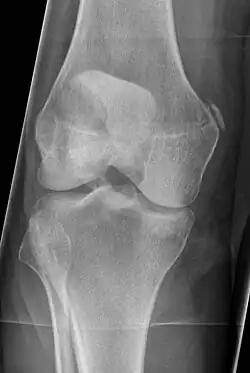

Different View of Pellegrini-Stieda Syndrome

Diagnosis is typically made on radiographs demonstrating the Pellegrini-Stieda syndrome sign accompanied by pain or restriction of range-of-motion of the knee joint.[2] Pellegrini-Stieda syndrome sign is typically described by a longitudinally linear opacity, which is a process that is describes characteristic of calcification in the soft tissue located medial to the medial femoral condyle.[2] This calcification seen on imaging represents the ossification of the medial collateral ligament, which typically does not develop until approximately three weeks after the initial injury.[2]It is important to note to distinguish this radiographic finding from that of a medial femoral condyle avulsion fracture, which is an injury in which a pulling force of a tendon or ligament fractures away a piece of the bone from its attachment site.[2]

Alternative classification syndrome for Pellegrini-Stieda lesions of Type 1 through Type 4 based on their location:[2]

• Type 1- is referred to as a beak-like appearance and describes the ossification arising from the femur and extending inferiorly in the medial collateral ligament.

• Type 2-is defines a tear-drop pattern, localized within the medial collateral ligament without any attachment to the femur.

• Type 3-presents as an elongated ossification superior to the femur lying in the distal adductor magnus tendon.

• Type 4-is also characterized as a beak-like appearance arising from the femur. However, there are some cases where this ossification extends into both the medial collateral ligament and adductor magnus tendon. In then, the original attribution of the syndrome to the medial collateral ligament may now be outdated as many publications have suggested concomitant and even sometimes preferential involvement of the adductor magnus tendon, medial head of the gastrocnemius, or medial patellofemoral ligament.[2]